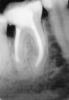

Ollegator Опубликовано 16 февраля, 2008 Поделиться Опубликовано 16 февраля, 2008 Здравствуйте! Сходил давеча в стоматологию по страховке с жалобой на боль в одном из зубов (это оказался 46-й - депульпирован 2-3 года назад - см. снимок).Врач, который меня смотрел, сразу сообщил, что зуб очень проблемный - и его, скорее всего, придётся рвать.Беда в том (как я понял), что протезирование делать нельзя, потому что "много крови", т.е. добраться до корня можно только сквозь слизистую, что сильно затрудняет работу, и не позволяет надёжно сделать цементирование.Второй врач (протезист) мне сказала, что гарантии на свою работу дать не может и посоветовала сходить ещё куда-нибудь, если я всё-таки хочу рискнуть сохранить зуб (рвать его целиком она жалеет, потому что "каналы хорошие"). А потом предложила попробовать сделать "гемисекцию" - как я понял, при этой операции удаляется часть зуба вместе с соответствующим корнем (плюсы: остаётся свой зуб, пусть и частично; минусы: может не получиться - и зуб "выйдет весь"; ползуба долго не проживёт, то есть это не спасение, а лишь отсрочка).Рисковать я, честно говоря, не хочу - и поэтому буду благодарен за советы знающих людей - что мне лучше всего сделать в моей ситуации:1. Есть ли возможность спасти зуб весь?2. Есть ли смысл в гемисекции вообще и в моём случае в частности? (имея в виду, что всё равно всё закончится имплантацией, причём, видимо, скоро)3. Если зуб всё-таки рвём весь - где и как делать имплантацию? (больше всего интересуют рекомендации конкретных людей и клиник в Москве)4. Куда ещё можно сходить показаться - возможно, существуют методы лечения именно для моего зуба (у меня он такой больной только один; цена - не главное) Время принять решение у меня есть до 20.02.2008 (на этот день уже назначена операция). Спасибо за помощь! С уважением,Олег Ссылка на комментарий